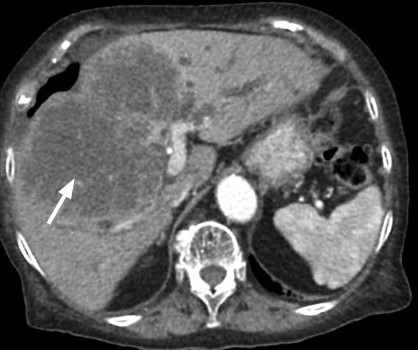

La hepatolitiasis se asocia con un aumento del riesgo de colangiocarcinoma intrahepático de 6 a 50 veces. La cirrosis se ha identificado como un posible factor de riesgo independiente para colangiocarcinoma intrahepático.